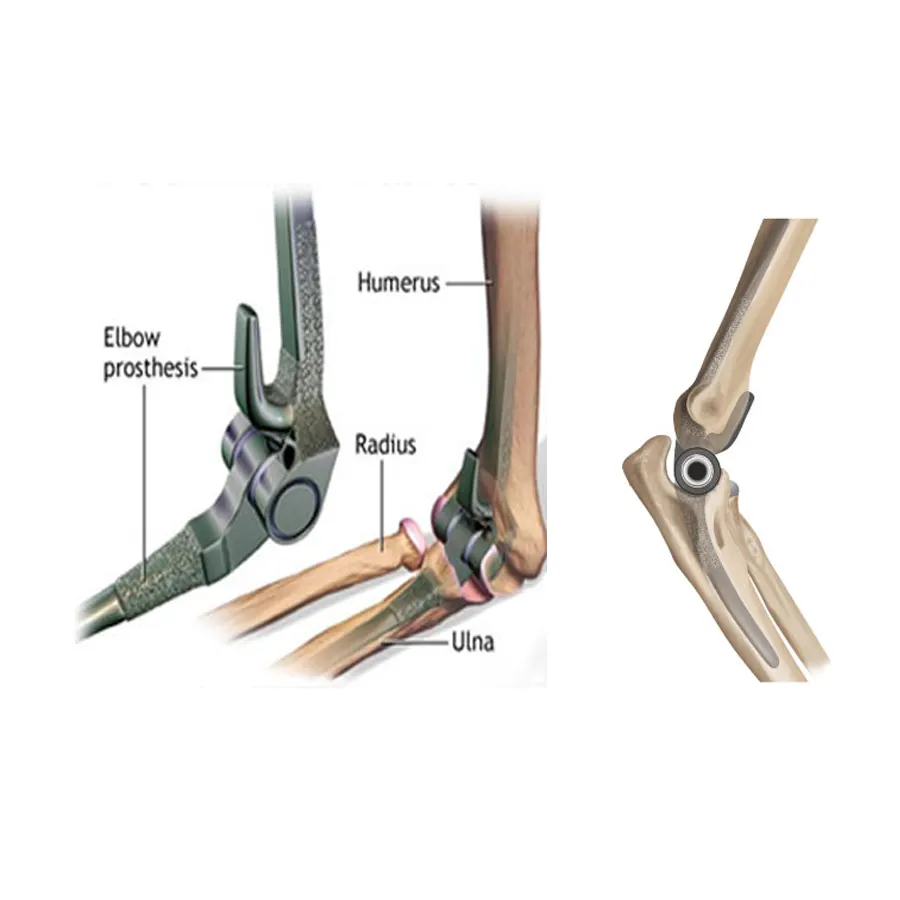

Most trusted, advanced, and affordable knee, hip, elbow, limb salvage surgery in India.

Dr Mujahid Saleem is an eminent Orthopaedic surgeon specialising in Joint Replacement Surgery, has exceptional Diagnostic and surgical skills operating now for over 35 years he has performed more than 20,000 surgeries using state-of-the-art techniques for optimum and functional recovery of his patients.